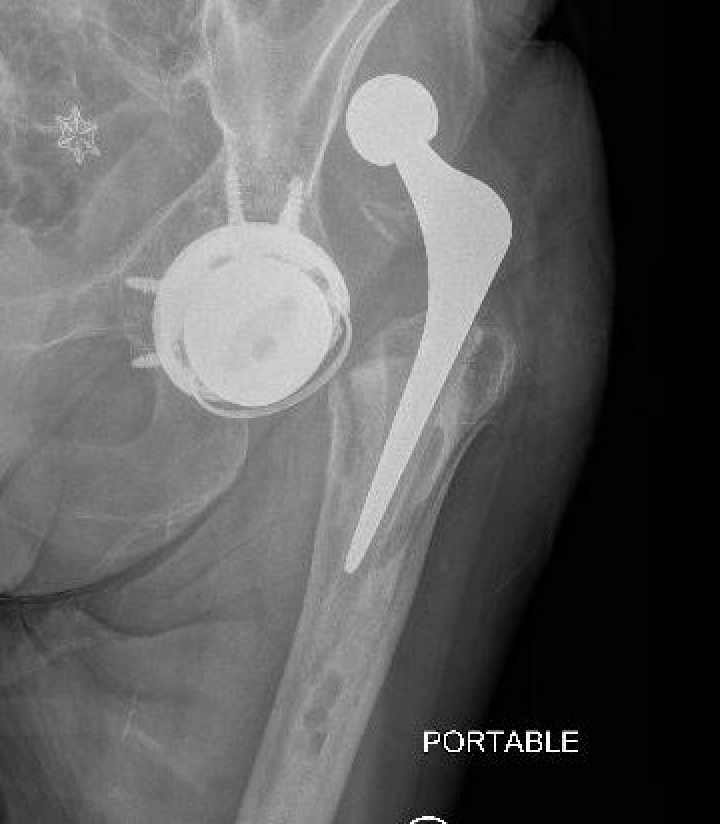

Dislocated constrained liner

Successful reduction constrained liner

Unsuccessful reduction constrained liner